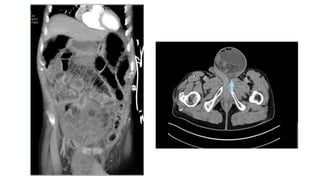

Diagnosis

• Pre-op: high index of clinical suspicion, notorious to be

missed on x-ray, confirmed on CT scan

• Intra-op: during exploratory laparotomy

Diagnosis • Pre-op: highindex of clinical suspicion, notorious to be missed on x-ray, confirmed on CT scan • Intra-op: during exploratory laparotomy